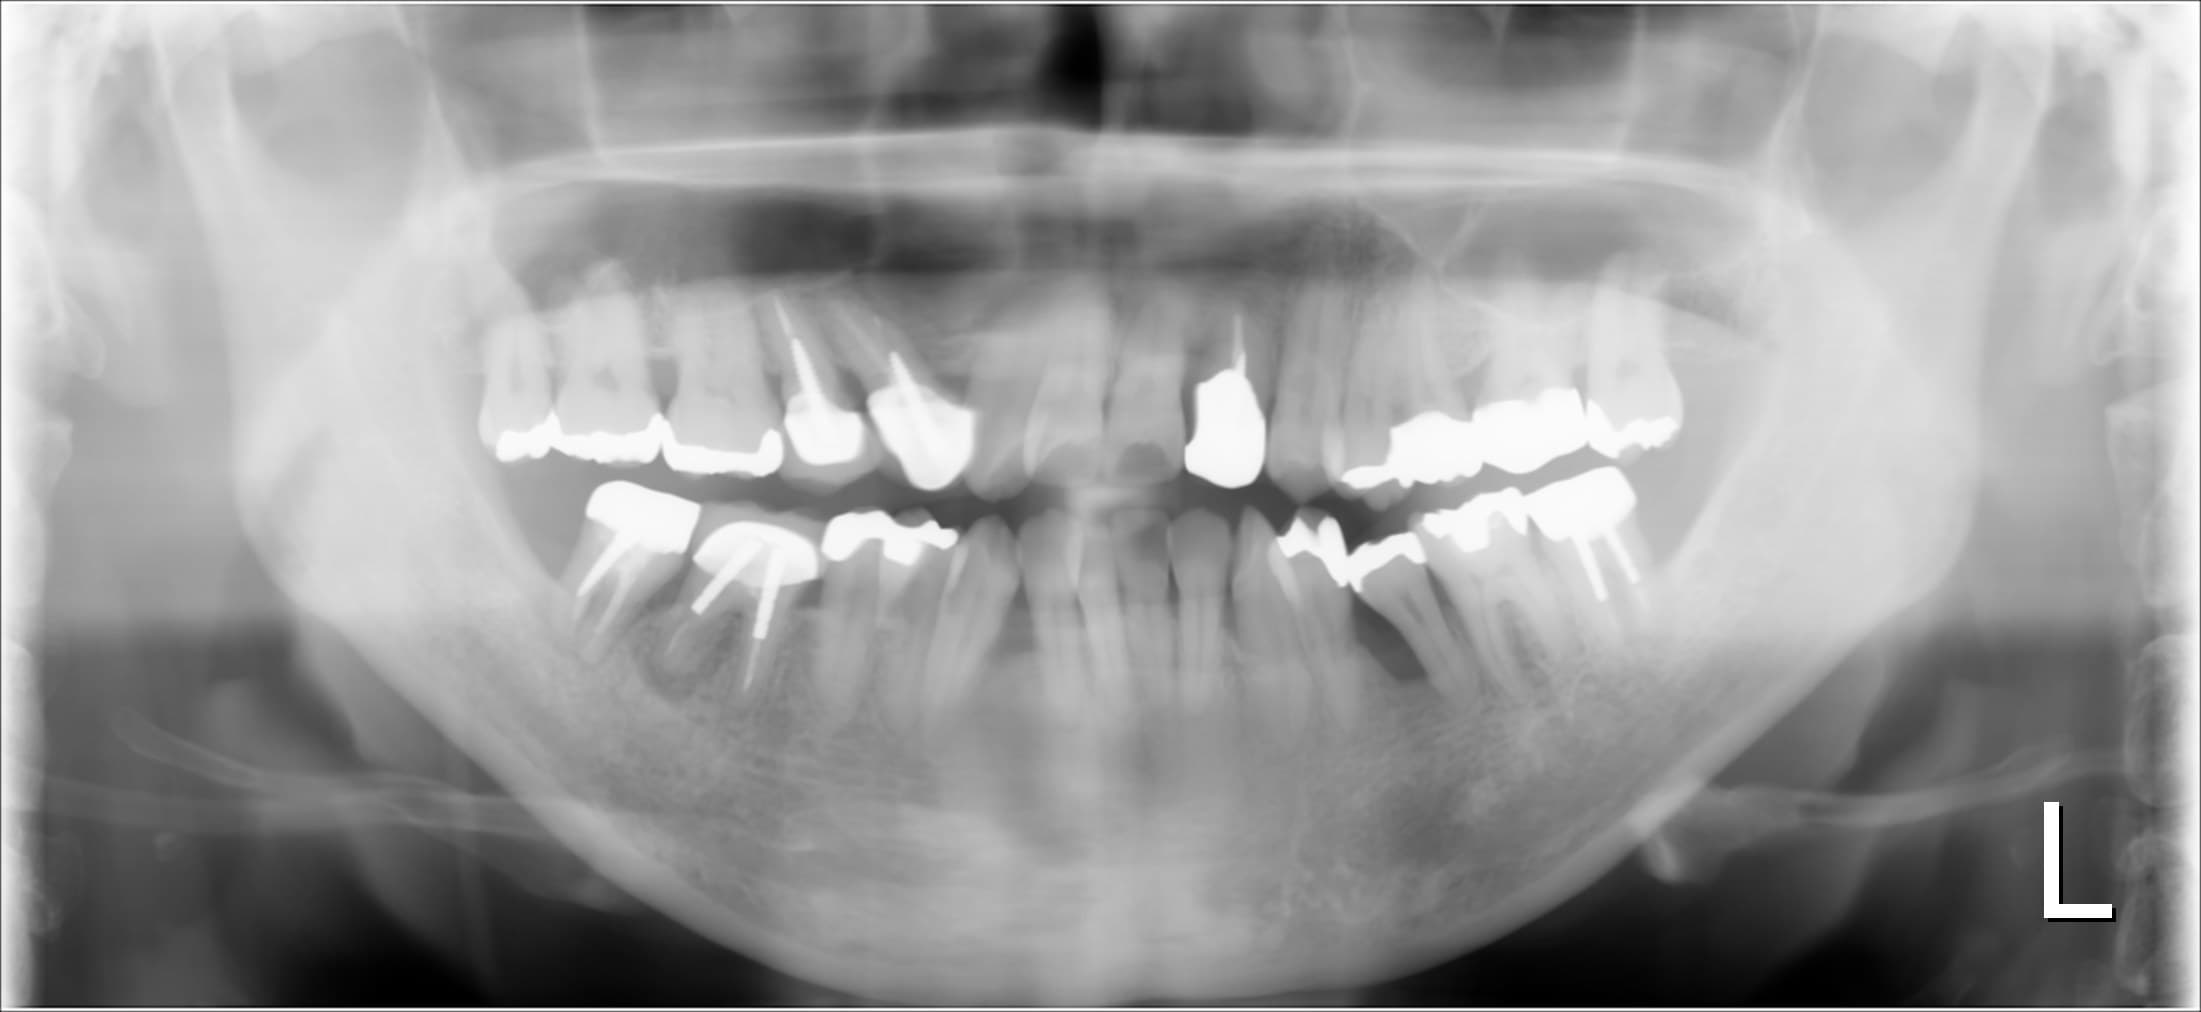

<治療前>

残念ですが、骨が大きく無くなっている所が数か所ありました。

ただ、沼地に家が建たない様に、骨の無い所に歯は建ちません。

それでも重症化してしまった歯周病は、残念ながら将来的に抜歯のリスクが高く残ってしまいます。